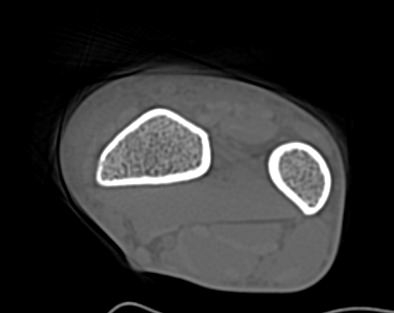

В компьютерном томографе излучатель рентгеновских лучей установлен в кольцевой части аппарата и, непрерывно вращаясь вокруг зоны исследования, производит послойное сканирование в различных плоскостях. В результате получаются снимки сустава в мельчайших подробностях, а после цифровой обработки полученных данных – точные трехмерные объемные модели исследуемой области. При этом изображения сустава можно приблизить, повернуть в разные стороны, что значительно повышает точность диагностики заболеваний костно-суставного аппарата.

В диагностических центрах «Доступная медицина» обследование суставов проводится на современных мультиспиральных компьютерных томографах экспертного класса TOSHIBA AQUILION. На аппаратах применяется методика скоростного мультисрезового сканирования, благодаря чему удается минимизировать дозу рентгеновского облучения для пациента, при этом обеспечить высокое качество изображений на снимках и трехмерных реконструкциях.